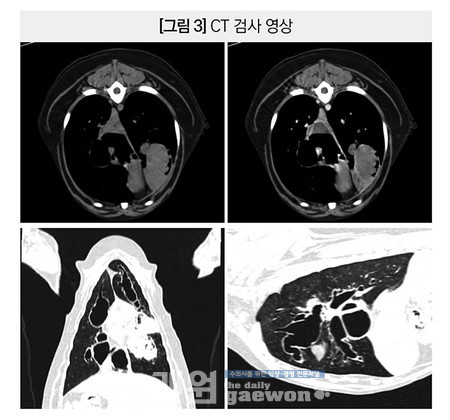

폐엽의 consolidation, torsion 또는 neoplasia의 가능성도 배제할 수 없어 CT 검사와 함께 기관지폐포 세척과 PCR, 배양,세포학 검사를 진행하였습니다.

CT 검사 결과,전반적인 기관지의 중증의 주머니형(saccular) 확장이 보였으며,중증으로 확장된 좌측 전엽 뒤쪽 부분 분지 기관지 내 세포성 액체 또는 점액,연부조직 밀도의 물질 충만이 확인 되었습니다.

확장된 기관지 벽의 비후와 다수의 기관지 내부에서 연부조직 밀도 또는 세포성 액체 밀도의 물질 충만이 관찰 되었습니다[그림3].